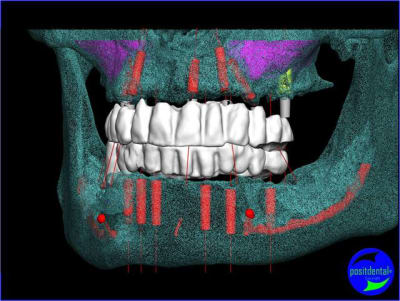

projet implantaire pour février

1er étape le wax-Up, dans ce cas clinique il est réalisé en 3D

guide de positionnement et intrado du bridge provisoire